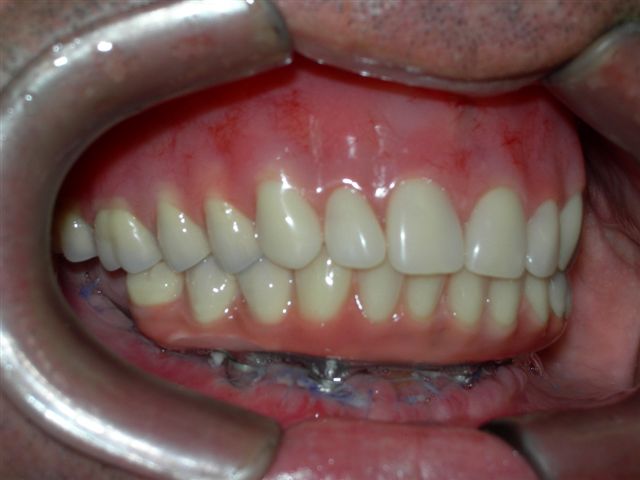

| Próteses antagonistas (VISTA DIREITA) |

Próteses antagonistas (VISTA ESQUERDA) |